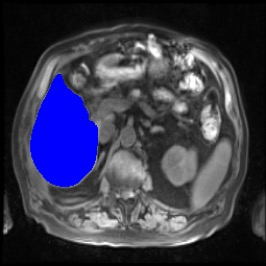

Integrating high-level semantically correlated contents and low-level anatomical features is of central importance in medical image segmentation. Towards this end, recent deep learning-based medical segmentation methods have shown great promise in better modeling such information. However, convolution operators for medical segmentation typically operate on regular grids, which inherently blur the high-frequency regions, i.e., boundary regions. In this work, we propose MORSE, a generic implicit neural rendering framework designed at an anatomical level to assist learning in medical image segmentation. Our method is motivated by the fact that implicit neural representation has been shown to be more effective in fitting complex signals and solving computer graphics problems than discrete grid-based representation. The core of our approach is to formulate medical image segmentation as a rendering problem in an end-to-end manner. Specifically, we continuously align the coarse segmentation prediction with the ambiguous coordinate-based point representations and aggregate these features to adaptively refine the boundary region. To parallelly optimize multi-scale pixel-level features, we leverage the idea from Mixture-of-Expert (MoE) to design and train our MORSE with a stochastic gating mechanism. Our experiments demonstrate that MORSE can work well with different medical segmentation backbones, consistently achieving competitive performance improvements in both 2D and 3D supervised medical segmentation methods. We also theoretically analyze the superiority of MORSE.

翻译:在医学图像分割中,整合高级语义相关的内容和低级解剖特征对于模拟这些信息非常重要。近期基于深度学习的医学分割方法已经显示出很有前景,可以更好地建模这些信息。然而,医学分割的卷积运算符通常在正则化网格上运作,这在本质上模糊了高频区域,即边界区域。我们在这项工作中提出了 MORSE,这是一个设计在解剖学水平上的通用隐式神经渲染框架,用于协助医学图像分割的学习。我们的方法的动机在于隐式神经表示已经被证明比离散化网格表示更有效地拟合复杂信号和解决计算机图形问题。我们方法的核心是将医学图像分割连续地对准粗糙的分割预测和模棱两可的基于坐标的点表示,并聚合这些特征来自适应地精细化边界区域。为了并行地优化多尺度像素级特征,我们借鉴了 Mixture-of-Expert (MoE) 的思想设计和训练我们的MORSE,使用随机门控机制。我们的实验表明MORSE可以很好地与不同的医学分割后骨干结合在一起,始终在2D和3D监督医学分割方法中实现了有竞争力的性能改进。我们还从理论上分析了MORSE的优越性。